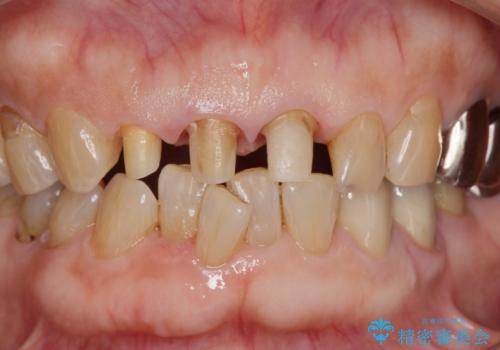

前歯の審美改善

- 70代女性

- 1ヶ月

- 2-5回

- 孫娘の結婚式に合わせて前歯を綺麗にして写真映りをよくしたいと来院されました。

結婚式に合わせて根管治療からのやりかえを短期集中治療で計4回で終える計画を立てます。